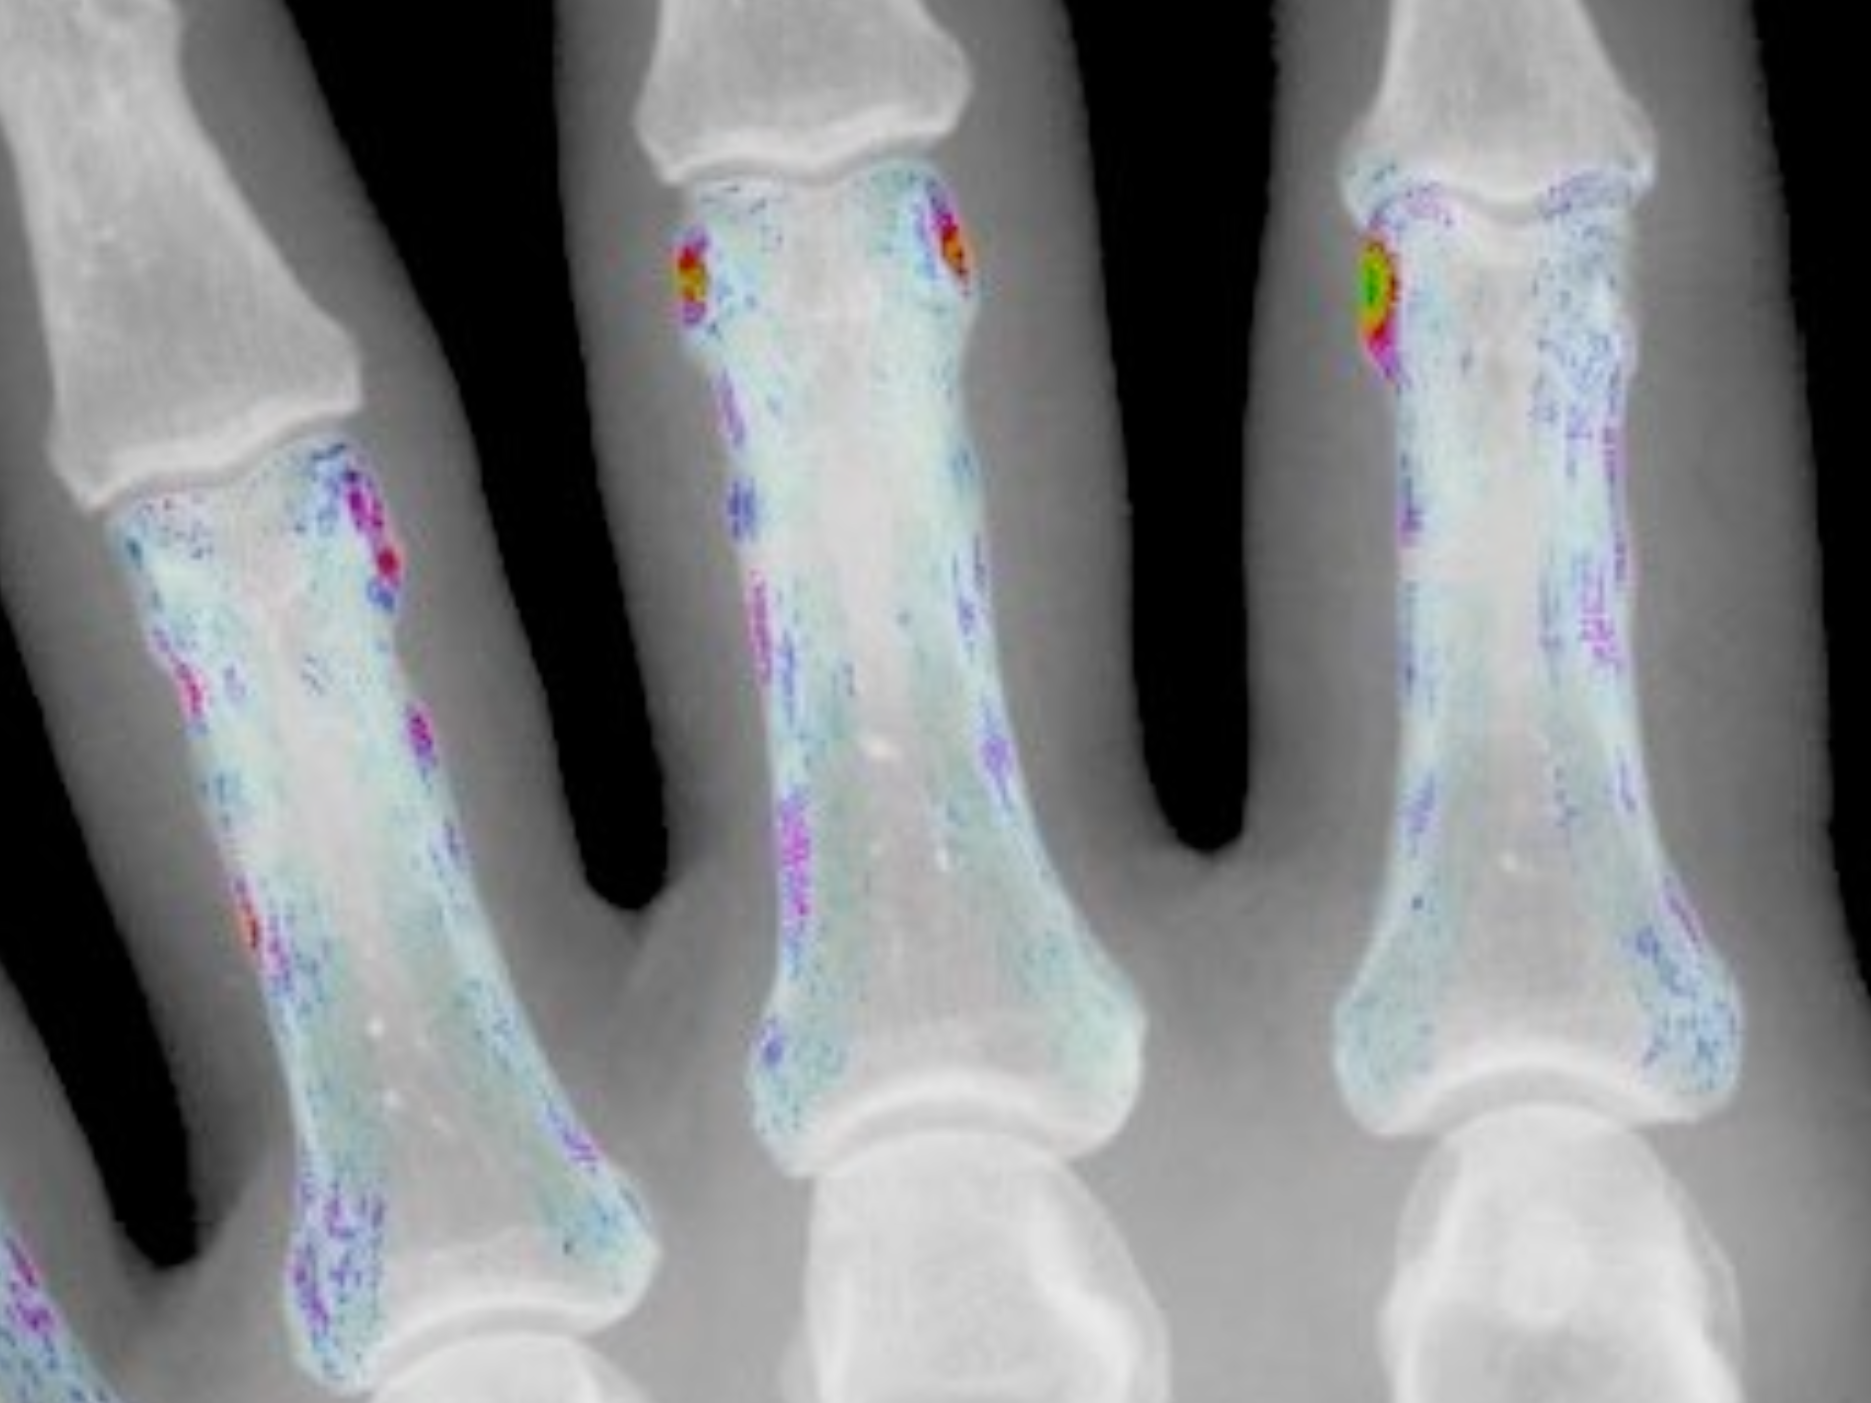

AutoPIX

AutoPiX has started in Nov 2024 and will connect imaging and AI to improve the care of patients with arthritis. It will develop novel technologiy in automated image analysis, therapy monitoring and prediciton, and the creation of foundation models to boost science and care in the area of arthritis.